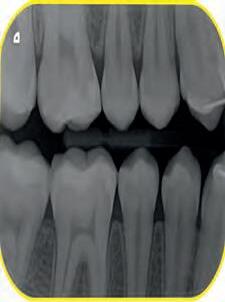

A 27-year- old male was admitted to the Endodontic Department of [Redacted] Medical Center for the past three days pain in the right front region. Medical history was noncontributory. Patient gave a history of spontaneous pain lasting from a few seconds to several hours. Also, pain is caused when hot and cold liquids are used, and is felt longer and more pronounced when hot, while cold relieve pain. Clinical examination revealed a carious cavity lesion penetrating the pulp of tooth # 43 (lower right canine). Tooth was tender to percussion. No swelling or fistula intra or extra orally. A diagnosis of irreversible pulpitis was made. Careful examination of the radiograph demonstrated a long root and the possibility of more than one canal (Fig.1)

Fig.1